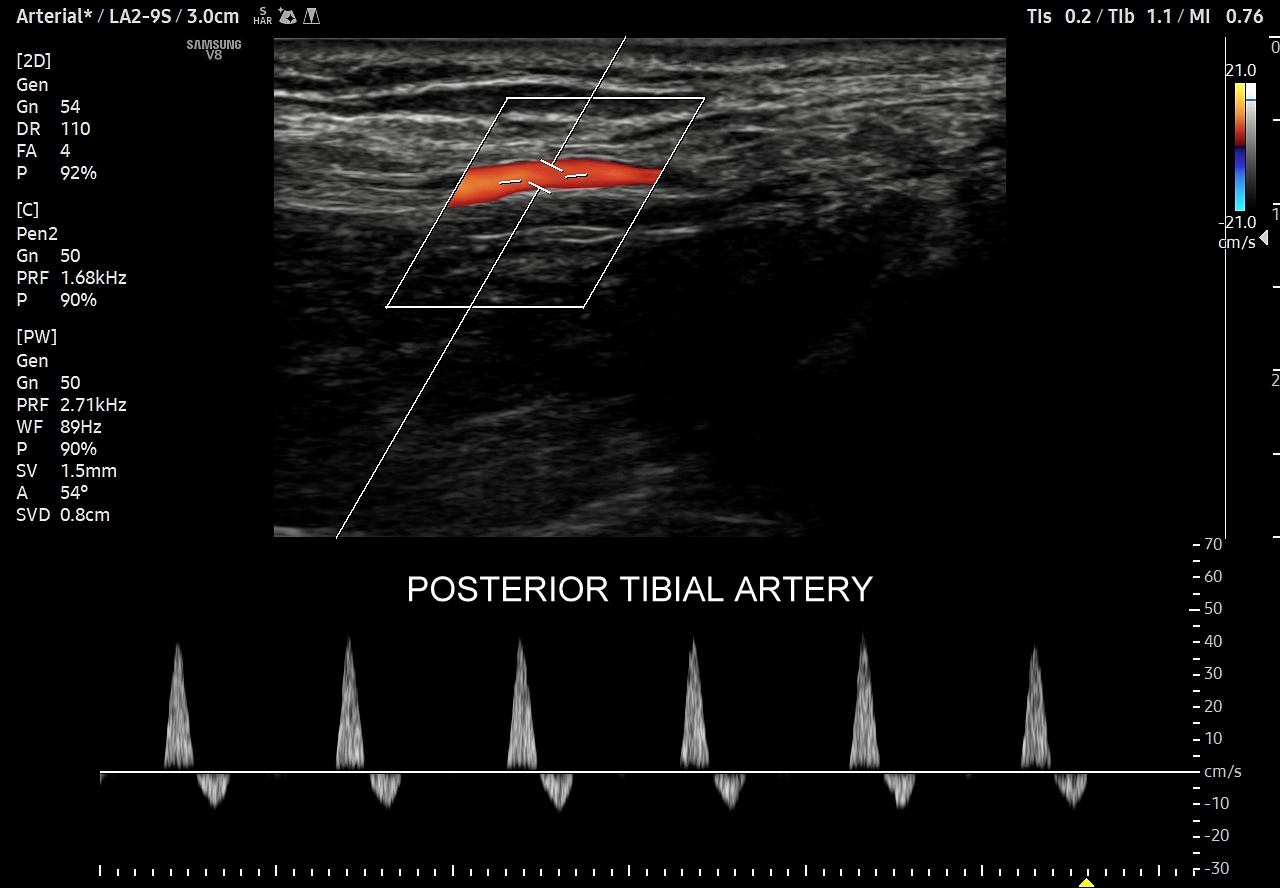

- Z kolei profile o wysokiej pulsacyjności charakteryzują się tym, iż posiadają wąskie i ostre piki skurczowe, a w fazie rozkurczowej odwrócone lub/i nieobecne przepływy. Profile tego typu występują w tętnicach unaczyniających kończyny.

W przypadku tętnic podążających do kończyn w warunkach spoczynkowych obserwuje się charakterystyczne wielozałamkowe profile przepływów zawierające od 2 do nawet 4 następujących po sobie przeciwstawnych załamków o zmniejszającej się amplitudzie, przy czym w tętnicach tych zwykle nie obserwuje się ciągłego przepływu w fazie rozkurczowej. Stały lub prawie stały przepływ rozkurczowy, tj. przepływ o pośredniej pulsacyjności, może pojawić się w tętnicach kończyn w trakcie intensywnego wysiłku fizycznego.